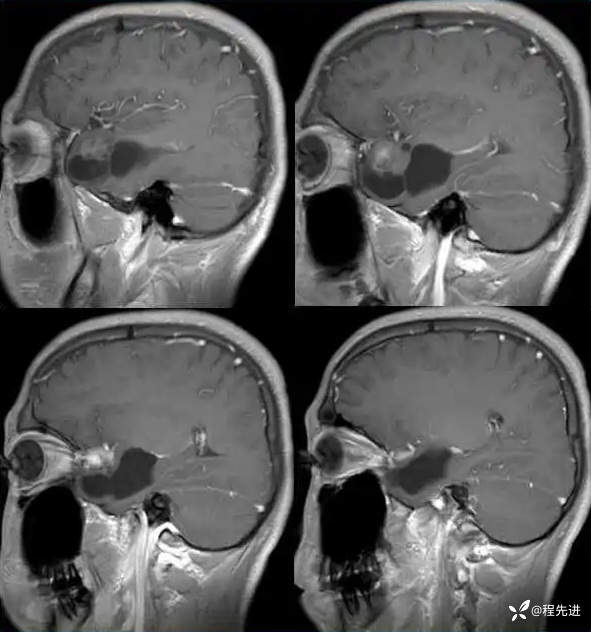

现病史:患者10天前无明显诱因突发四肢抽搐伴意识障碍,发作时口吐白沫,牙关紧闭,大约5分钟后患者清醒,醒后不能回忆发作时情况,查头颅MRI检查提示右侧颞叶占位。门诊拟“继发性癫痫”收住入院。患者病程中无明显头痛头晕,食纳睡眠可,大小便可,体重无明显变化。

T1:

T1增强: